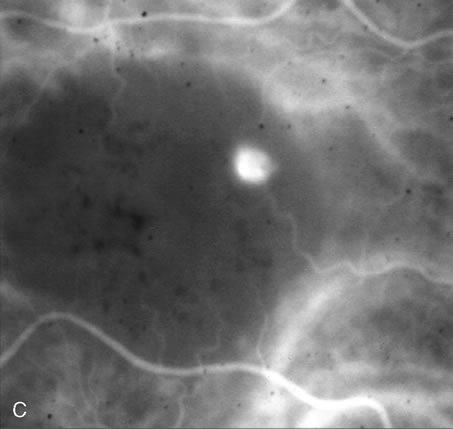

The differentiation of a partial-thickness, or lamellar, macular hole from a full-thickness macular hole can be challenging, and FA is often helpful in assisting in the diagnosis.55 As in a full-thickness hole, a lamellar hole presents as an excavation of the retina, and the presence of drusen underneath the lamellar hole can simulate the yellow deposits seen at the base of full-thickness holes. Occasionally, there is a full-thickness hole at one side of a lesion, and the rest of the lesion consists of a lamellar defect. FA will show immediate hyperfluorescence from the choroidal circulation under a full-thickness hole (Fig. 34A), whereas a lamellar hole, with a relatively intact RPE, will block some of the normal fluorescence from the choriocapillaris (Fig. 34B).

Fig. 34. Full-thickness and partial macular holes. A. There is a discrete hole in the central macula. Hyperfluorescence reflects choriocapillaris leakage that is normally partially blocked by retinal pigment epithelium. B. There is partial blockage of the choroidal hyperfluorescence, but subtle hyperfluorescence is visible. (Courtesy of Dr. Peter Judson.)